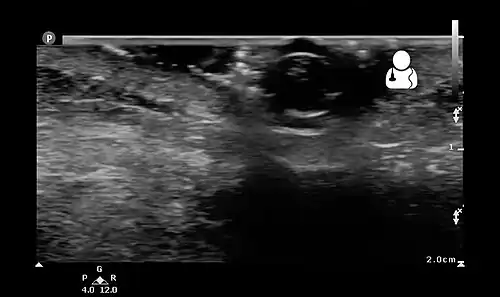

-

Ultrasound showing maggot infestation[24]